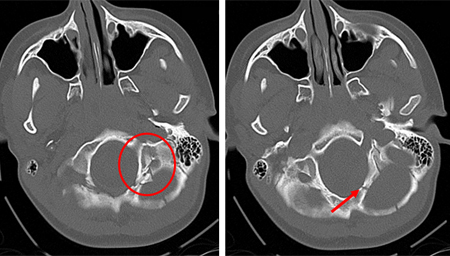

Fratura occipital se estendendo até o forame magno: risco de compressão do tronco encefálico por hematoma.

Do acervo de aulas de Demetrios Demetriades, Division of Trauma and Surgical Intensive Care, LAC/USC Trauma Center, Keck School of Medicine da USC; usada com permissão